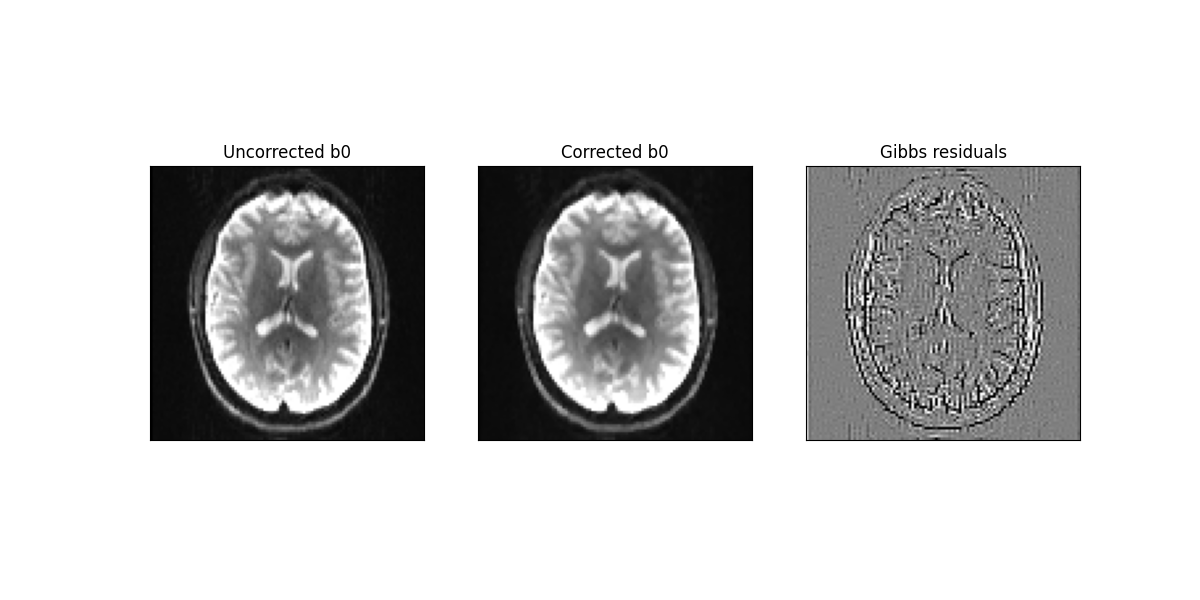

Below we plot the results for an image acquired with b-value=0:

Uncorrected (left panel) and corrected (middle panel) b-value=0 images. For reference, the difference between uncorrected and corrected images is shown in the right panel.

The above figure shows that the benefits of suppressing Gibbs artefacts is hard to observe on b-value=0 data. Therefore, diffusion derived metrics for both uncorrected and corrected data are computed using the mean signal diffusion kurtosis image technique (Mean signal diffusion kurtosis imaging (MSDKI)).